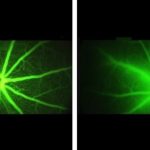

Study: Experiments show new therapy slows blood vessel leakage associated with diabetic macular edema...

In studies with lab-grown human cells and in mice, Johns Hopkins Medicine researchers have found that an experimental drug may be twice as...